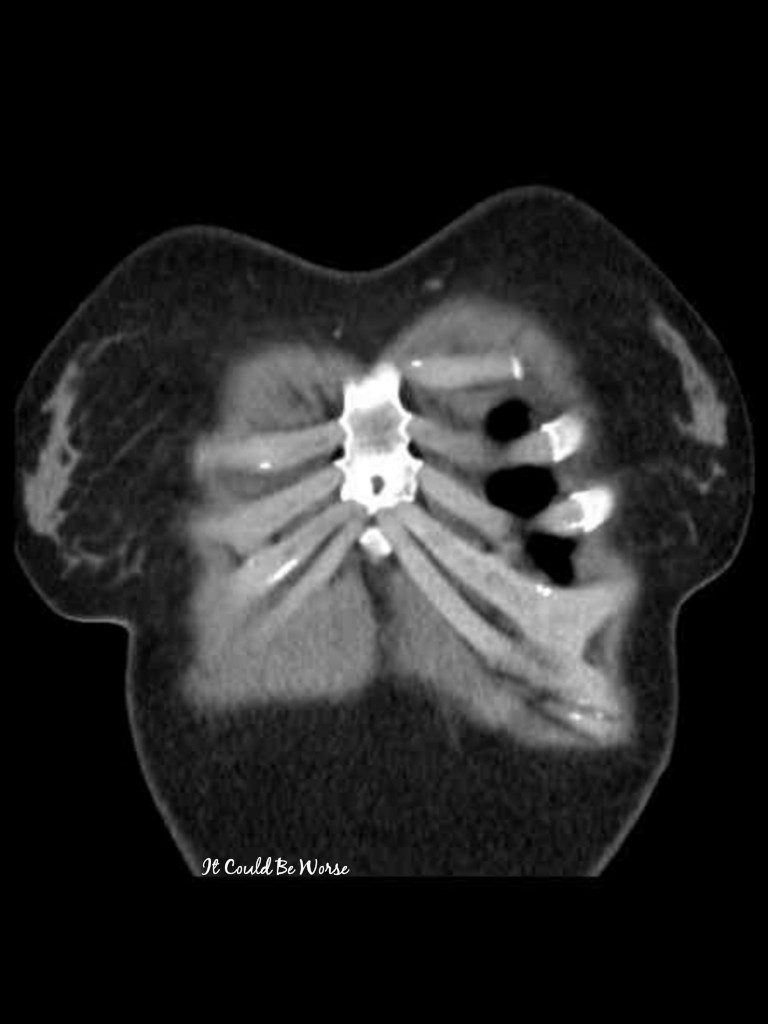

I know that I had surgery this past January to remove the titanium plate and we resected the tip of my slipping/dislocated 10th rib. My surgeon sutured my 10th to my 9th and we hoped for the best. Mind you, this was my third thoracic surgery trying to correct my slipping rib and rib pain.

Now, 4 months later, I am still having problems with these ribs. In my mind, I figured it was the 11th rib starting to slip up and under my 10th – as my body has been shifting and settling into its new ‘normal’ position post-surgery.

So, with my current surgeon feeling confident and understanding Dr Hansen’s procedures, we understand that the sutures used last time to connect my 10th rib to the above ribs, it may be sawing through my rib and letting that rib slip under once again. I may have moved or shifted wrong, it could have broken through, or it could be my 11th rib slipping.

I can only tell by touch – but I think my 10th has worked its way loose with the sutures cutting through the bone and cartilage, and allowing it to slip, with the 11th now rubbing against it.

Even if the sutures have not cut through my ribs already, they still need to be replaced. If it is my 11th rib, we will fix that problem once my chest wall is opened again. We have no idea what is exactly wrong until we get inside my body. Imaging tests don’t like to show that rib cartilage in the front of your body, so we end up going in blind and finding out the problem in surgery.